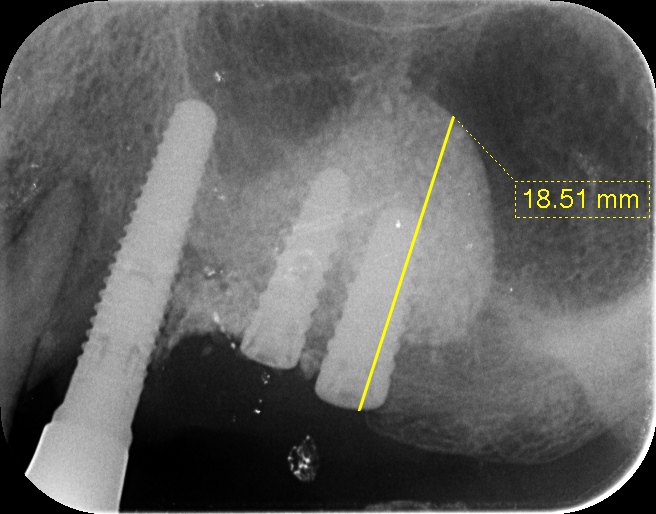

2021年5月19日の症例78歳男性左うえ56ラ…

【患者様の主訴】 10年前に他の歯科医院で施術していただいたインプラントブリッジが6か月前から相次いで脱離、左上、右下、右上、前歯と脱離してしまった。再インプラントするには骨がやせているので、入れ歯を進められました。インプラントにしたいのでラテラルスリットを左うえに、またすべてのインプラントを骨…